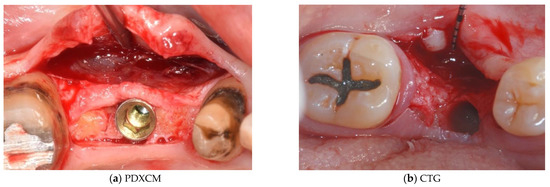

| Papi et al. [27] | 12 patients | Prospective cohort study | 12 months | N R | PDXCM: 1.25 |

| Zafiropoulos et al. [38] | 27 patients | Prospective, randomized examiner-blinded controlled clinical study | 6 months | N R | PDXCM: 1.06 |

| Stefanini et al. [39] | 10 patients | Case series | 12 months | PDXCM 0.65 ± 0.41 | PDXCM: 1.2 ± 0.18 |

| Papi and Pompa 12 [40] | 12 patients | Prospective pilot cohort study | 12 months | PDXCM: 4.32 | N R |

| Schmitt et al. [41] | 14 patients | Controlled clinical trial | 6 months | N R | PDXCM: 0.30 ± 0.16 |

| Verardi et al. [42] | 24 patients 24 implants | Prospective study | 6 months | PDXCM 1.33 ± 0.71 | N R |